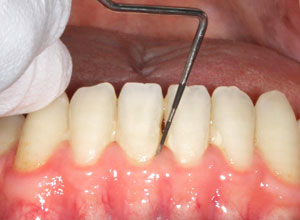

(1)歯周組織検査

専用の器具を使って、右の写真のように、

歯周ポケット(歯と歯ぐきの間)の深さや、出血、歯が動いていないかなどを調べます(

※少しチクチクする程度で痛くはありません)。